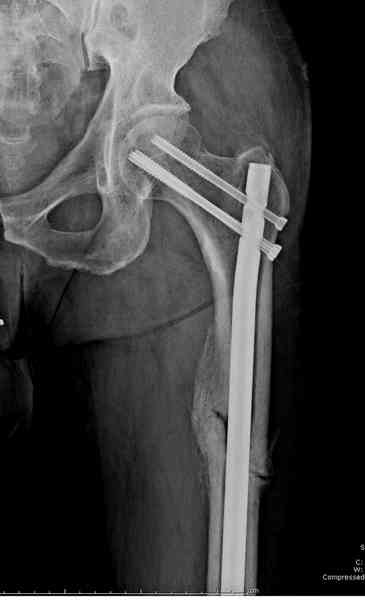

В первый же день произведено антеградное штифтованием DePuy Trochanteric Nail.

На второй день (7) обнаружен пропущенный перелом,

и проведены шурурпы через и спереди штифта без удаления.

Послеоперационные снимки